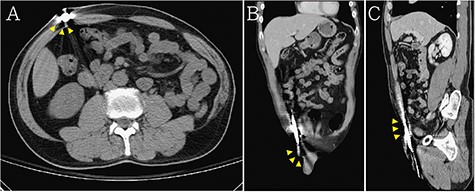

A 55-year-old man presented with traumatic injury due to a foreign object penetrating his scrotum when he slipped and fell. This foreign object was a steel bar that penetrated his left scrotum and extended to his abdomen (Fig. 1A and B). Upon physical examination, his blood pressure, heart rate and Glasgow Coma Score were 122/75 mmHg, 131 beats/min and E4V5M6, respectively. Laboratory investigation indicated leukocytosis (10 700/ul, normal range: 3900–10 400/ul) and no anemia. A portable radiography reading showed that the penetration extended from the left scrotum to the right abdomen but indicated no injury to the pelvic bone or spine (Fig. 1C). An abdominal computed tomography (CT) scan demonstrated that the penetration extended from the left scrotum to the right anterior abdomen wall (Fig. 2). Emergency surgical removal of the steel bar was performed for debridement and repair. First, two skip incisions were created on the tip and middle portion of steel bar. Subsequently, curved Kelly forceps were used for guiding with a Jackson-Pratt (JP) drain to prevent wrong placing tract and gently removed the steel bar (Figs 3 and 4). Thereafter, the wound was irrigated with copious normal saline, and the bleeders were then checked. No additional injury was found in the peritoneum, testes and spermatic cord. Blood loss was minimal (<5 ml). No immediate intra-operative complications were noted. The patient received intravenous broad-spectrum antibiotics after surgery and was discharged on the fifth day after the operation with fair convalescence.

Abdominal CT demonstrated that the penetration extended from the left scrotum to the right anterior abdomen wall (the steel bar: yellow arrow head) in (A) axial view, (B) coronal view and (C) sagittal view.